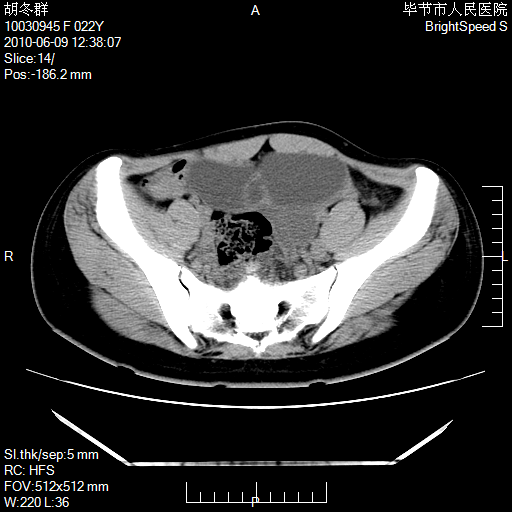

患者23岁,发现腹部包块3月。

左侧卵巢囊腺瘤或囊腺癌

盆腔内囊性占位性病变;考虑左侧卵巢囊腺瘤。

有分隔、壁薄,支持考虑左侧卵巢囊腺瘤。

左侧卵巢浆液性囊腺瘤。

支持考虑左侧卵巢囊腺瘤;宫腔积液。

有分隔、壁薄,支持考虑左侧卵巢囊腺瘤。排尿后,膀胱缩小,由于重力作用,肿块下移就到了膀胱位置,很好理解。